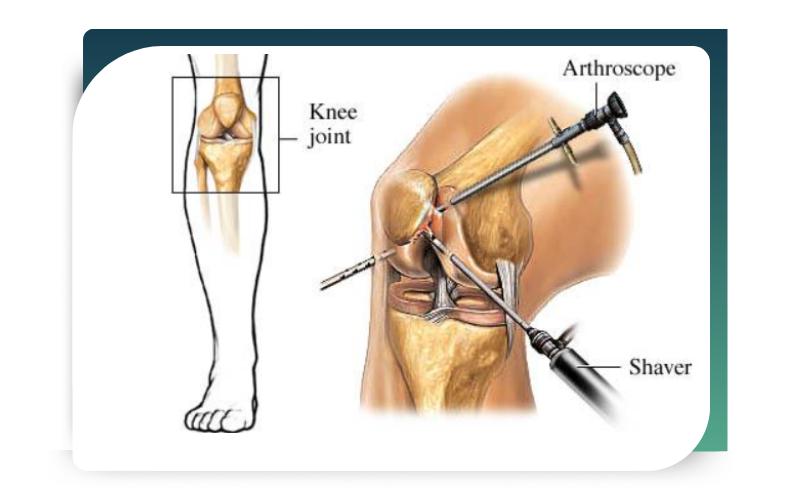

Knee Arthroscopy

Knee injuries are among the most common sports-related problems. Twisting movements, sudden stops, or direct impact can damage ligaments and cartilage within the knee joint.

Dr. Abhishek Bhalotia performs advanced knee arthroscopy procedures to treat:

Through keyhole surgery, damaged tissues are repaired or reconstructed with high precision. Post-surgery rehabilitation programs are customized to ensure optimal strength, flexibility, and joint stability.

What Is Arthroscopy?

Arthroscopy is a minimally invasive surgical procedure used to diagnose and treat joint problems. During the procedure, a small camera called an arthroscope is inserted into the joint through tiny incisions. This allows the surgeon to view the internal structures on a screen and perform precise repairs using specialized instruments.

Unlike traditional open surgery, arthroscopy offers: